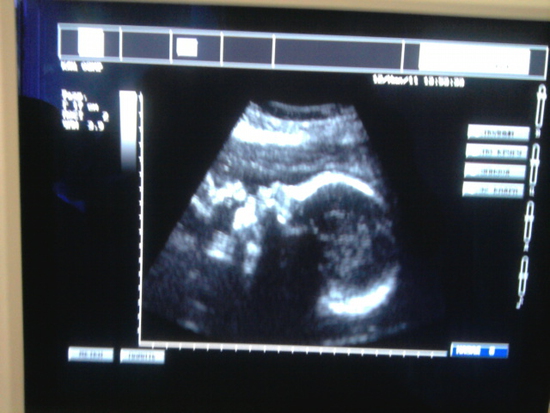

Ну и о самом Узи наконец-то. Самое главное, придлежание у нас головное! Ну и девочка все таки (хотя лично у меня сомнений и не было), а то очень многоие говорили что парень, несмотря на то что и на УЗИ 2-го триместра уже девченку отлично было видно))) Срок на момент УЗИ был 31 нед. 6 дней. Вес 1650) Сердцебиение 147 уд/мин. Плацента расположена по задней стенке, толщина 36 мм, степень зрелости I. И опять вопрос к тем, кто знает что это за степень зрелости такая?

Ну и фото моей крохи, профиль моей красавицы) Простите за качество, фотка в попыхах на телефон.